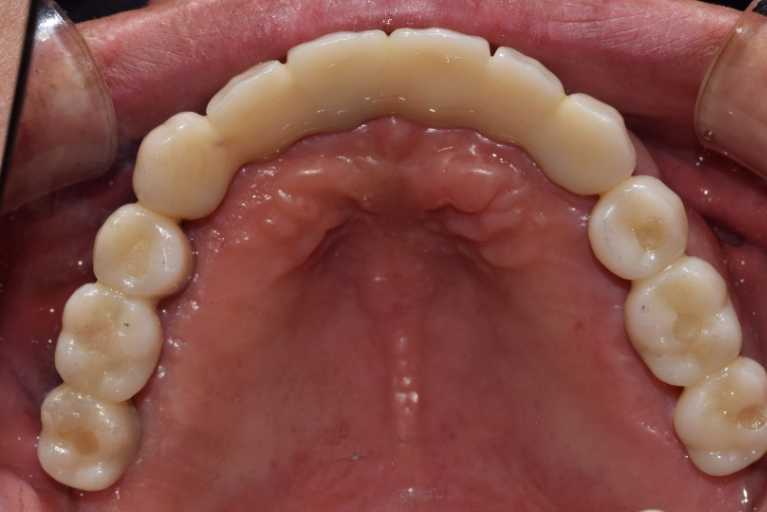

무치악 임플란트 전후 실제 사례 #3

#무치악 임플란트 환자 사례 : 기존 치아의 염증 상태로 인해 치료 시작일 때, 잔존치 전체 발치 + 상악동거상술(양쪽) + 뼈이식다수 + 임플란트 픽스처(뿌리) 17개 식립